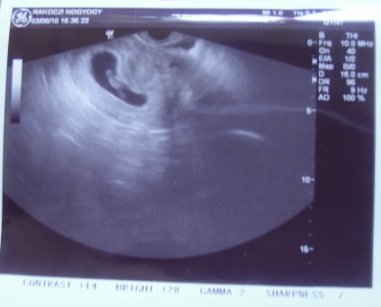

Még a péntekről: BMC: Ápr. 2-án voltam HSG-n, (pénteken). A párom is velem volt, mert nagyon izgultam, mert mondták elég kellemetlen érzés.... Kaptunk az eleján fájdalomcsillapító tablettát, (nem volt kötelező) de azért mindenki kért. Egyszerre négyünket vizsgáltak.

Aztán egyeztetés után átmentünk a központi röngenbe (1 épülettel arrébb - János Kórház) Ott sorba mentünk be, miután megint volt némi eligazítás... Én voltam az utolsó, mert a Dokimat meg kellett várni, a másik 3 lánynak másik doki csinálta a vizsgálatot.

Szóval nekem egyáltalán nem volt vészes, a fájdalmat tekintve, ezek szerint nem is voltam elzáródva, pedig egy csomó kontrasztanyagot kaptam. aminek egy része vissza is folyt... Szóval az eredmény jó lett. A doki meg nagyon jó fej volt!!!! Örülök hogy őt választottam.

a lényeg hogy ha később fontos lenne az vezetők átjárhatósága azt csak kisműtéttel tudják megnézni, mert az nem látszott a felvételen.. de ez nekünk most nem is kell.. egyébként meg csak gyanítja, hogy átjárhatóak, mert nem fájt egyáltalán...